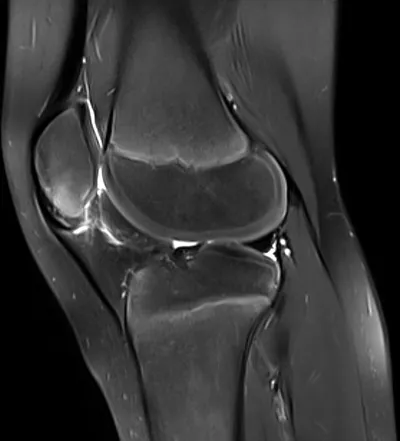

Black PD cartilage sign - chondrocalcinosis in chondral fissure

MRIKneeAxial+2